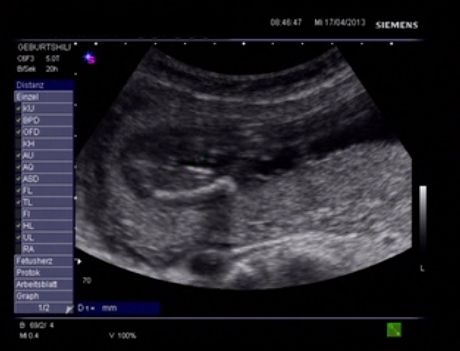

Hello Everyone! Its me again :-) A Gender swaying friend (wanting a Girl) made the The Baby Gender Predictor Test: Am I having a boy or girl? DNA - Test And it said -> BOY! Her second son is 19 Months old and she was pretty careful making the test... Now she went to her doctor’s appointment and the doctor was sure it’s a Girl!! What do you think? Picture 1 : (NT-Scan – Baby Nr.3 -> Is the current pregnancy ) Sohnemann 2 is her second Boy ;-) Picture 2: 17 weeks pregnant potty scan the arrow should show the girl parts .... So Ladys what do you think any chance itīs a GIRL??? Greetings & Thanks ....

Attachment 10345